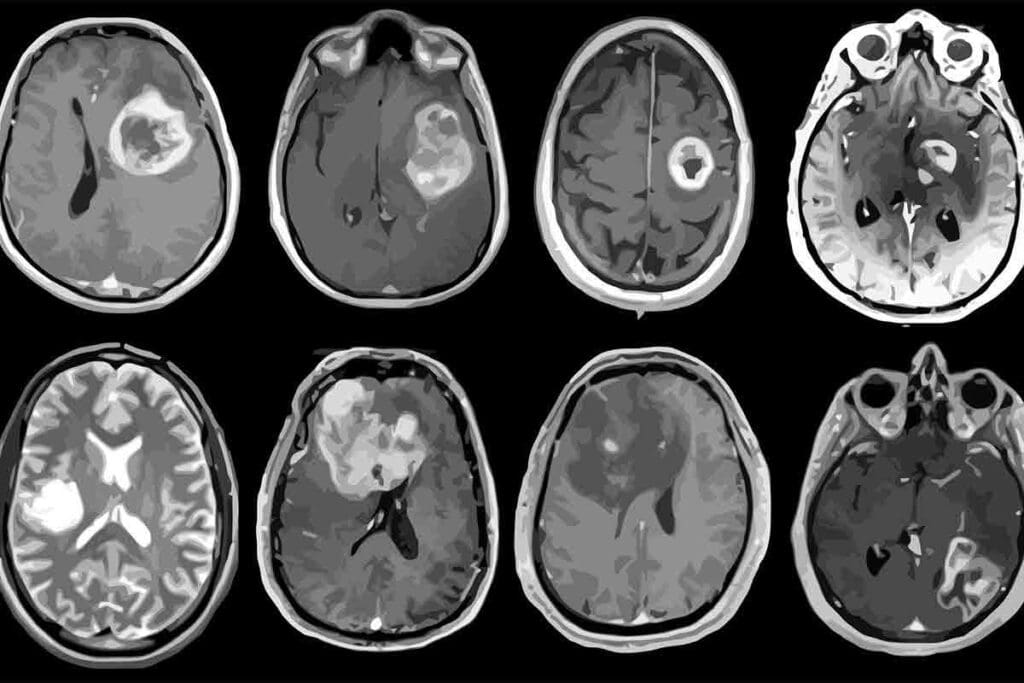

Advanced Imaging Techniques

Advanced imaging is vital for diagnosing glioblastoma multiforme. Magnetic Resonance Imaging (MRI) is the main tool used. MRI gives clear brain images, showing the tumor’s size and its effect on the brain.

At times, Computed Tomography (CT) scans or Positron Emission Tomography (PET) scans are also used to get more details.

Biopsy and Pathological Analysis

A biopsy is key to confirming the diagnosis. A neurosurgeon takes a tumor sample. The sample is then studied by a pathologist to confirm the tumor type and grade.

This step is vital for knowing if it’s glioblastoma multiforme and how aggressive it is.